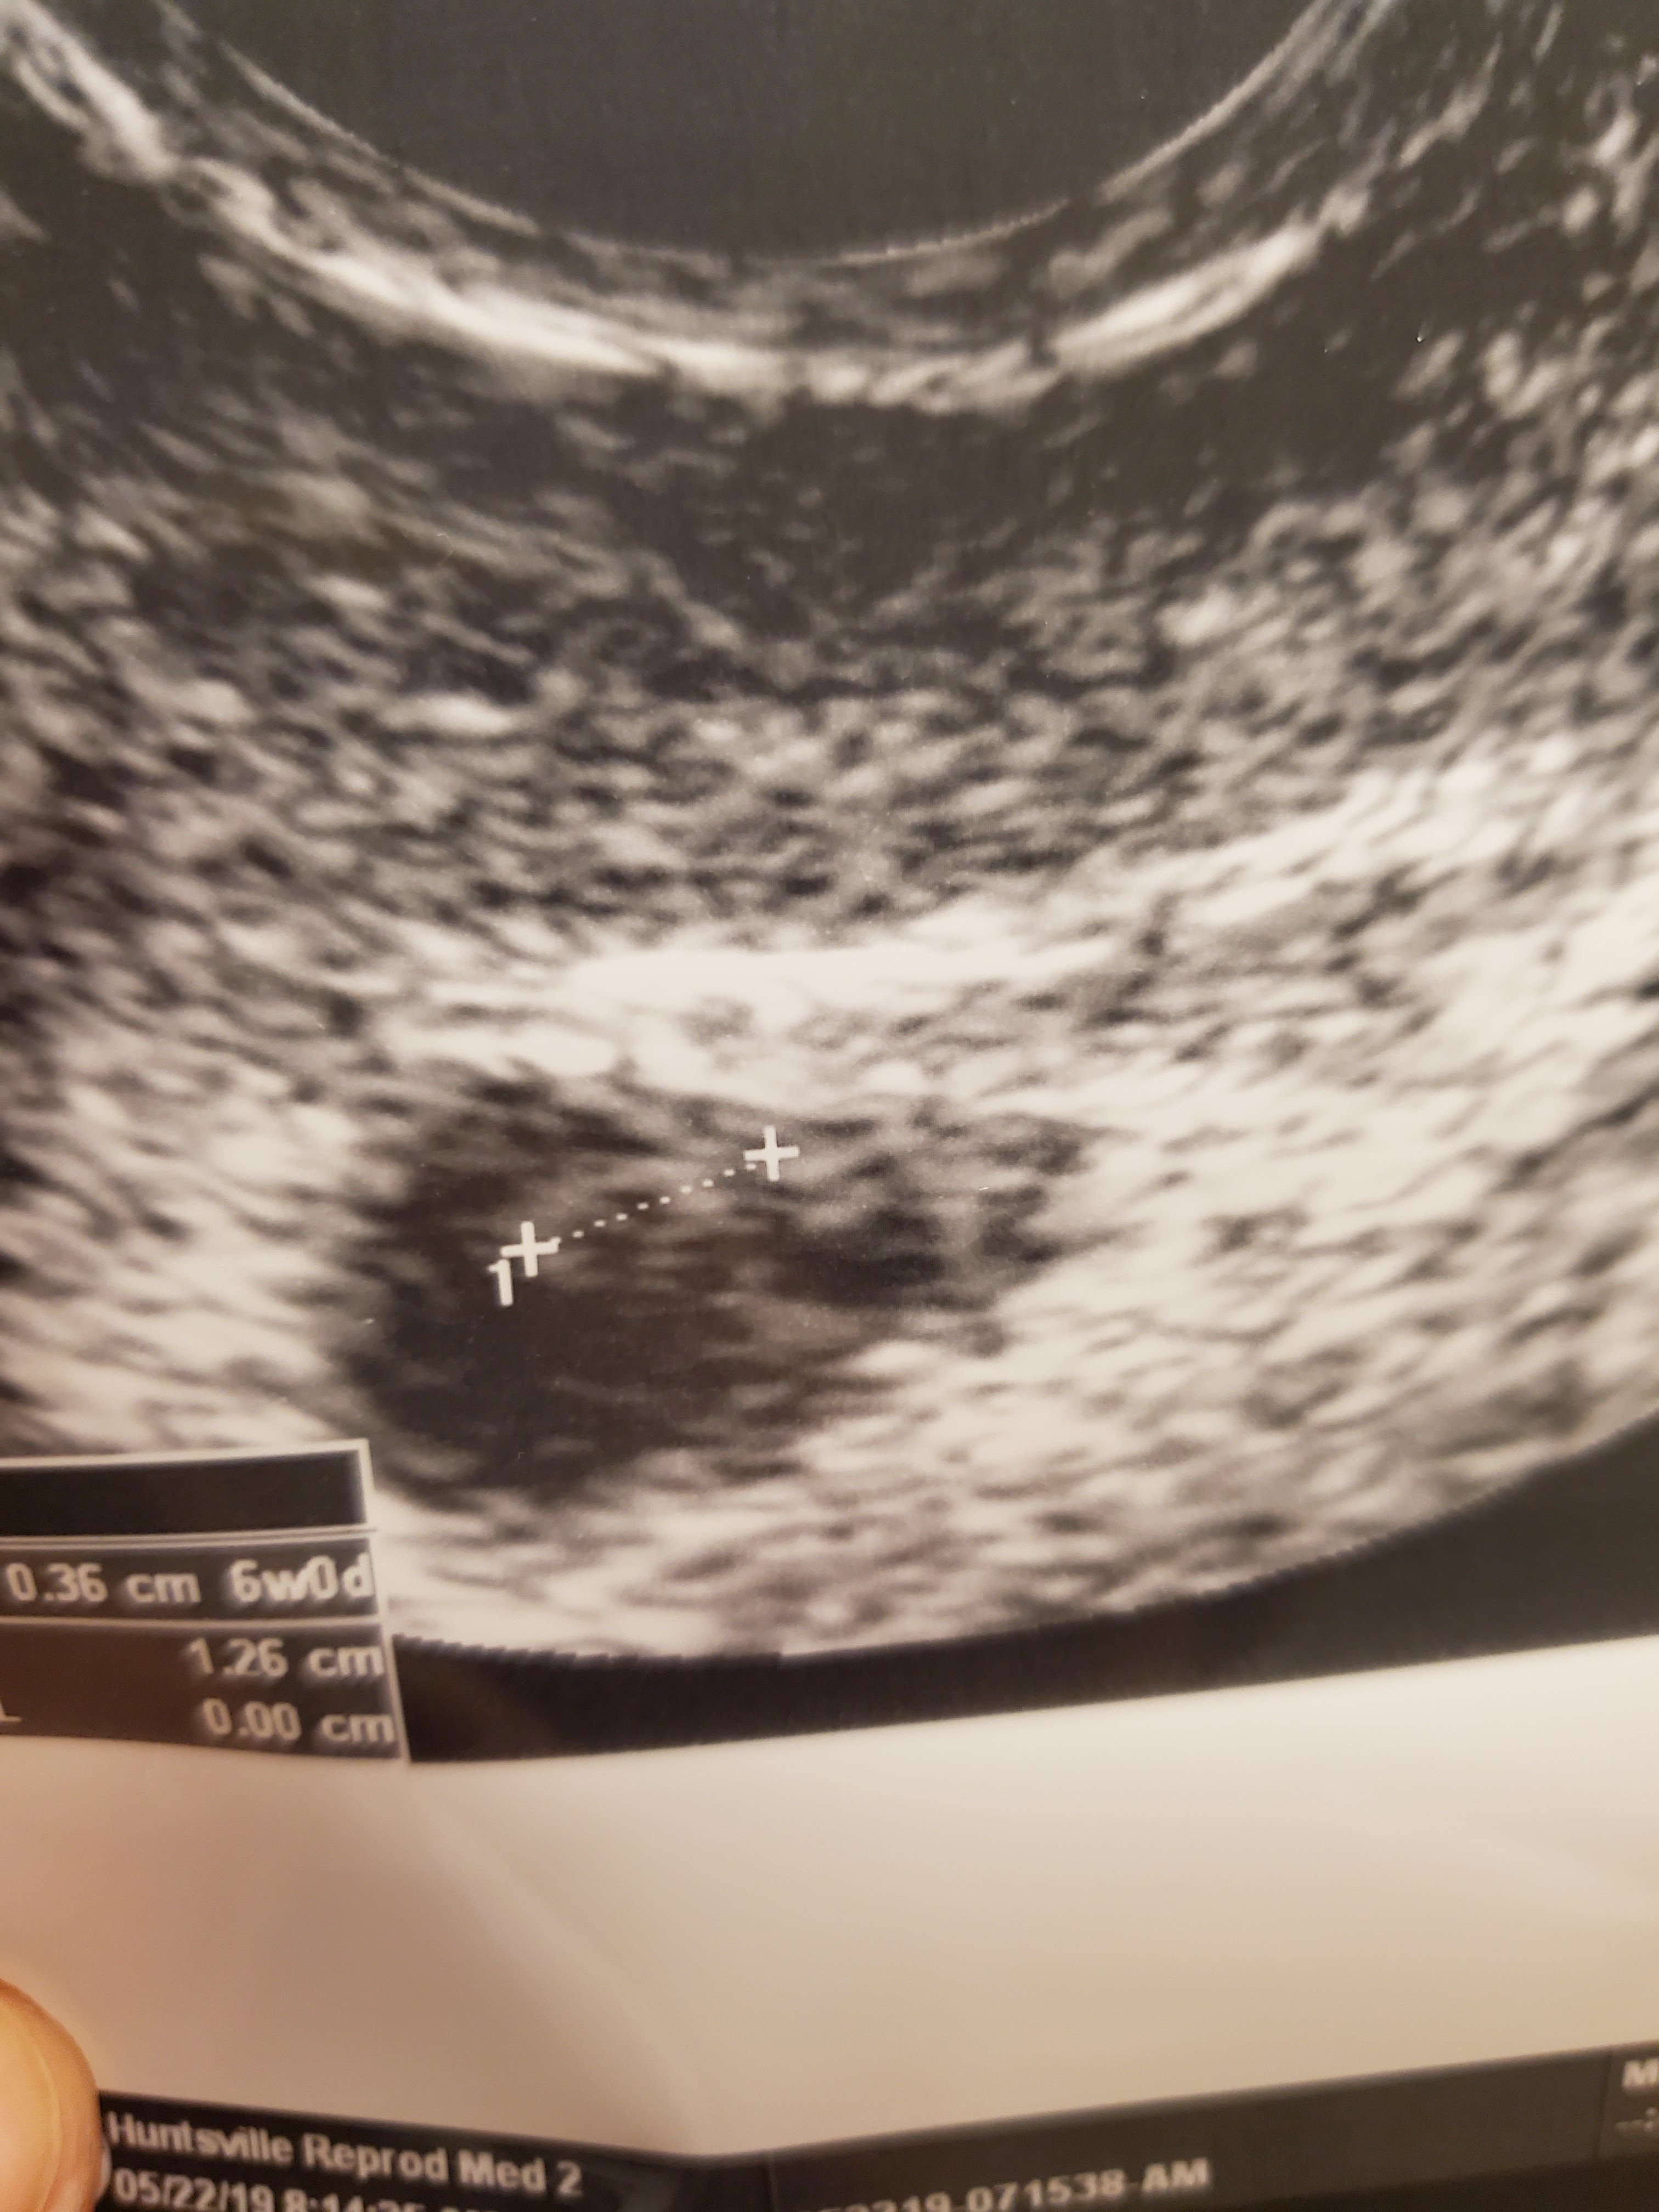

We have a healthy little bebe grub worm!!! 7 weeks and 122 beats per minute!! Longest weekend of my entire life all to end with wonderful news!!!!!